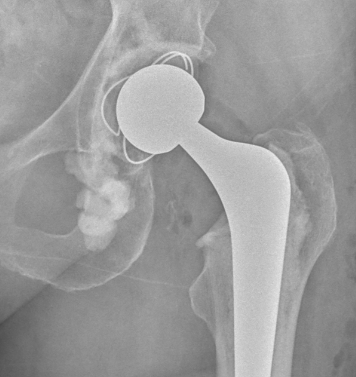

Zimmer ZCA all poly cup

Components

- all polyethylene

- spacers to ensure even cement mantle

- +/- flange to compress cement / prevent escape around cup

- metal insert to gauge position on xray

Types

- Smith & Nephew Reflection all Poly

- Styker Exeter X3 all Poly

- Zimmer ZCA all Poly

Exeter X3 S&N Reflection